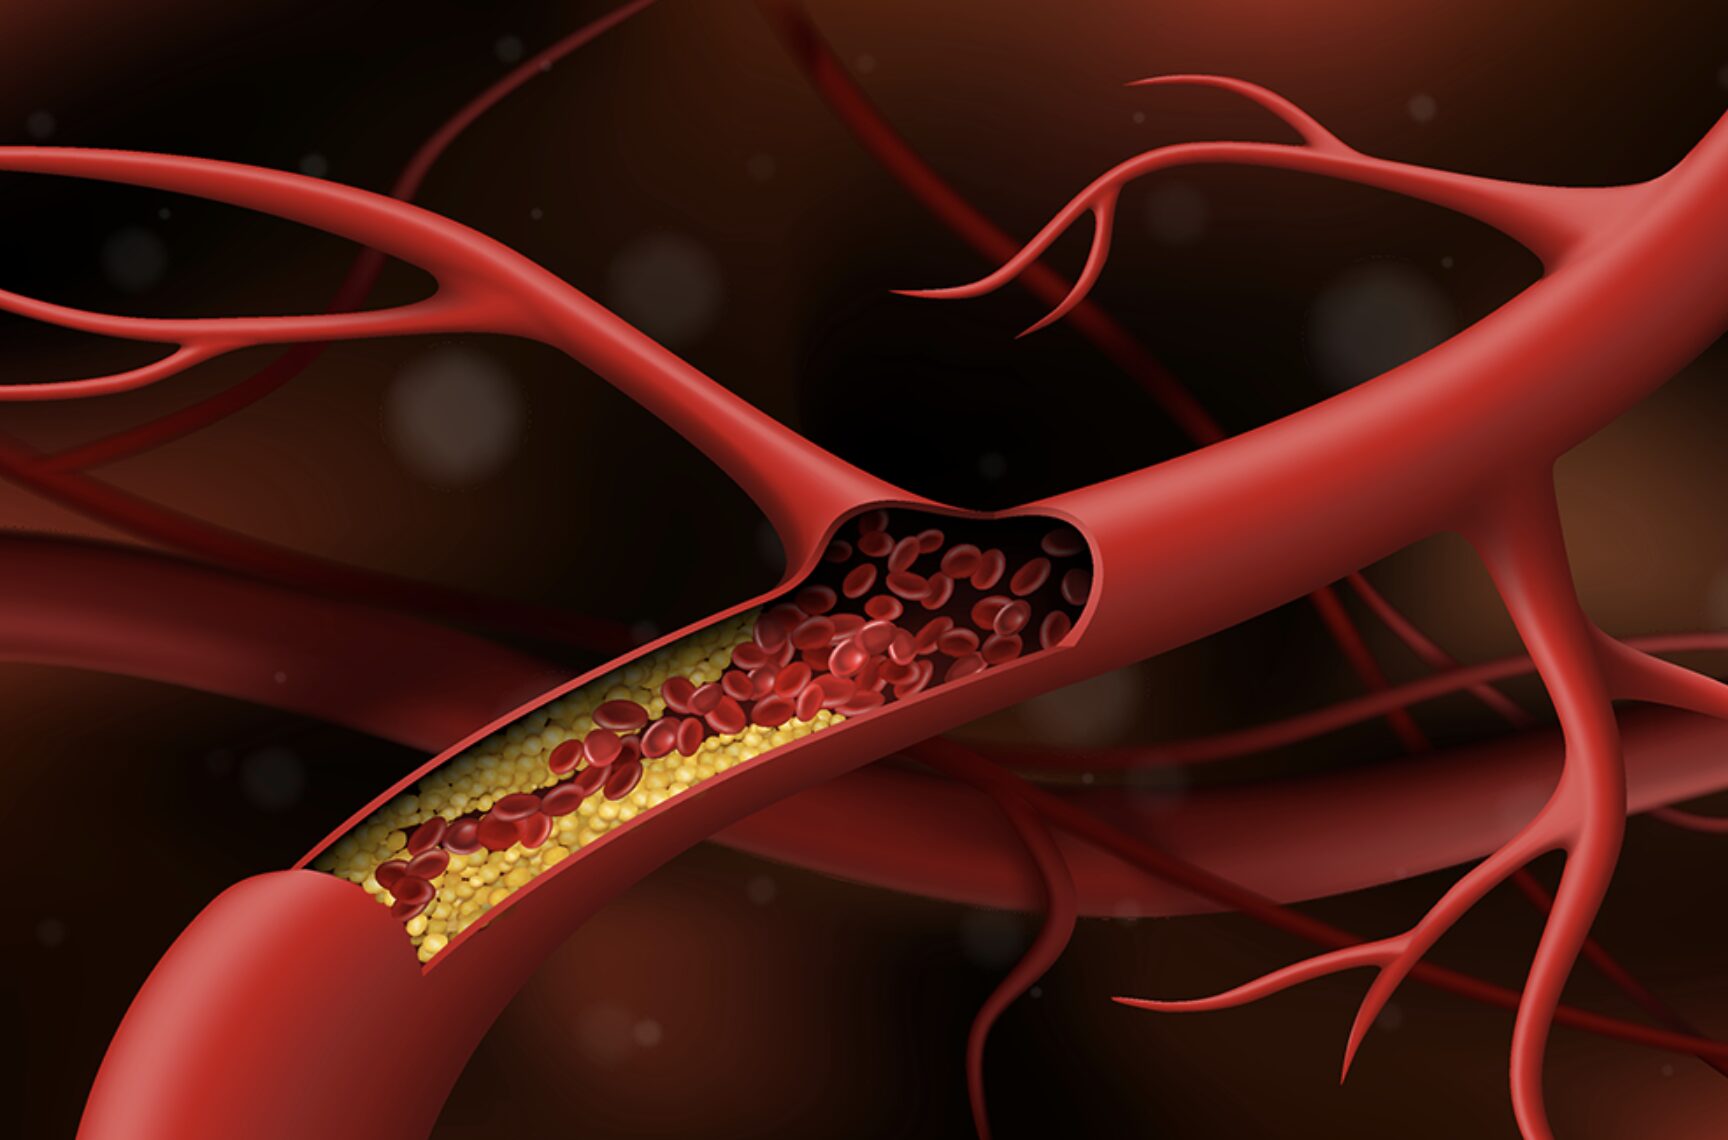

Tăng huyết áp, bệnh tim và đột quỵ có liên quan như thế nào?

Mặc dù huyết áp cao (tăng huyết áp) thường không có bất kỳ triệu chứng đáng chú ý nào, nhưng nó có thể gây tổn hại nghiêm trọng đến hệ tuần hoàn của bạn. Nếu không điều trị, nó có thể làm tăng nguy cơ mắc một số biến chứng nghiêm trọng, bao gồm bệnh tim mạch, đột quỵ và các tình trạng sức khỏe khác.